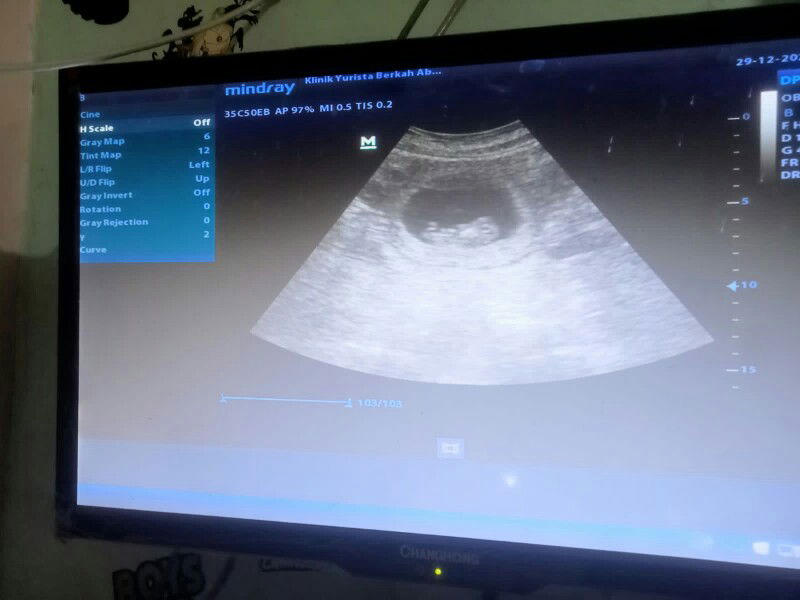

posisi janin

bun. usia kehamilan aku uda 19 minggu tapi posisi janinnya masih di bawah. Dan sekarang janinnya uda aktif banget, bentar² gerak. wajar gak sih bun 19 minggu janinnya masih dibawah?

Kayaknya sama deh bun soalnya minggu lalu aku usg ke dokterpun katanya posisinya masih kurang bagus, banyakin posisi kayak lagi sujud katanya, sama ngepel (saran dari dokternya)